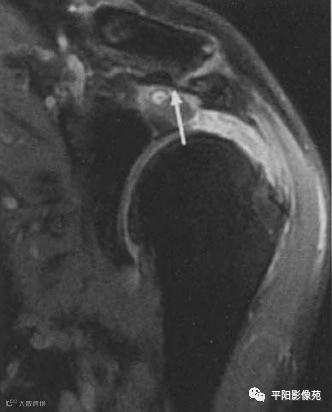

肌腱全层撕裂,示例

2、冈上肌肌腱全层撕裂,肌腱断端回缩,肩峰下-三角肌下滑囊积液